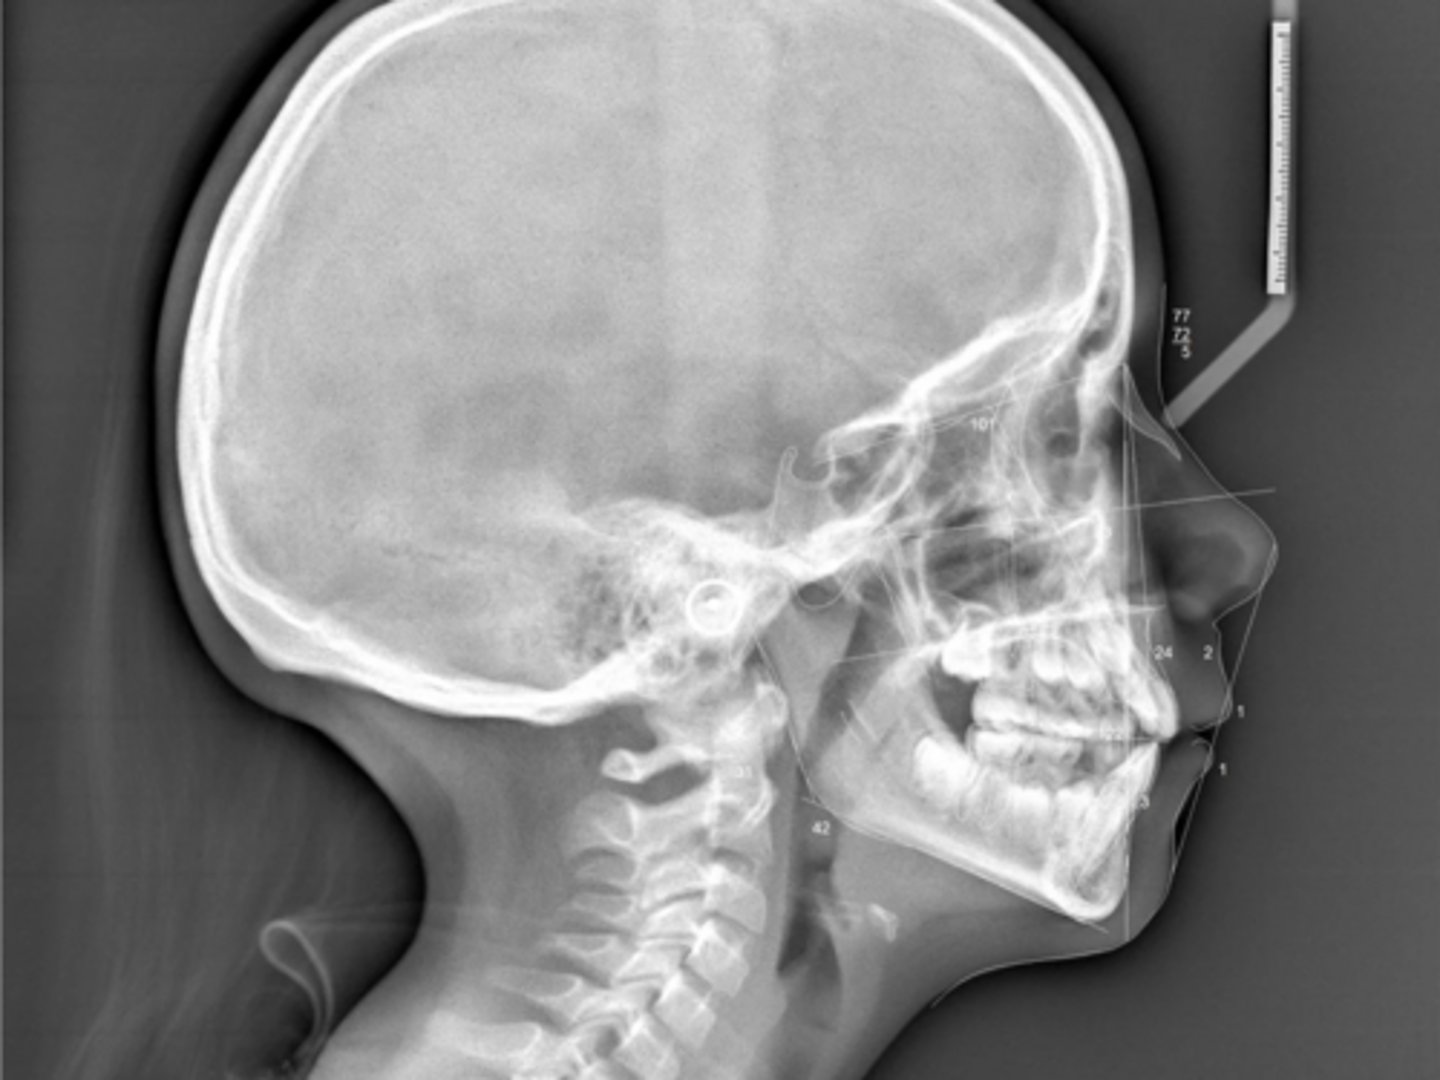

Class II

What type of skeletal malocclusion is this patient?

Hyperdivergent

Are the hyper-, hypo-, o normo- divergent?